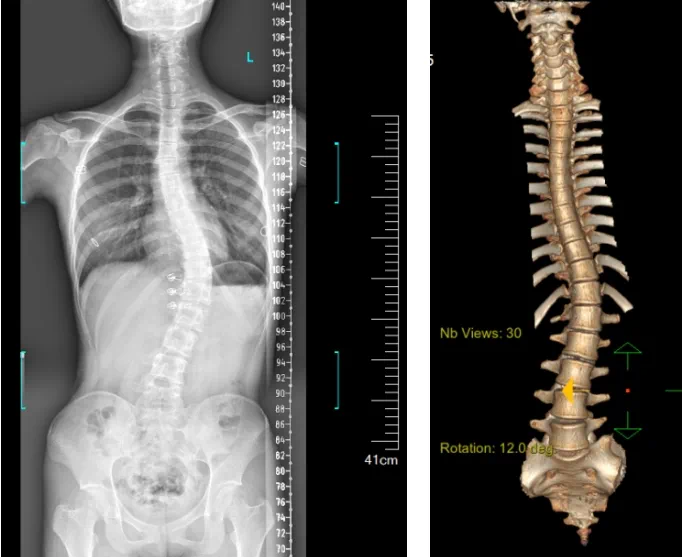

患者為一名16歲女孩,發現脊柱側彎1年,到南方醫院贛州醫院脊柱外科求診。經查體,患者左右胸廓不對稱,雙肩等高,左肩胛骨隆起,背側呈“剃刀背”畸形,胸腰段棘突偏離正中線,胸腰段脊柱左側凸畸形;各棘突無壓痛及叩擊痛,右側腰部凹陷,胸腹及腰背部感覺正常。檢查發現患者特發性脊柱側彎,Lenke5C型,主胸彎51°。患者及家屬對外觀不滿意,為改善外觀及功能,要求手術矯形治療。

WechatIMG3428.jpg